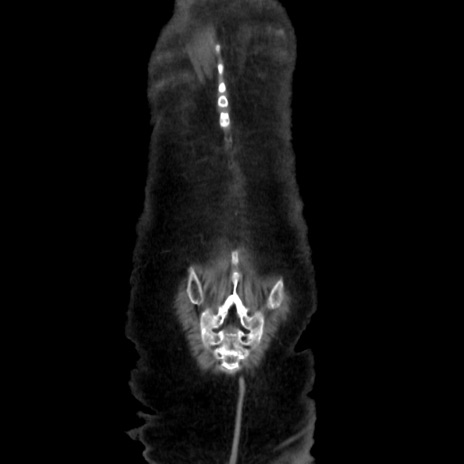

症例40(冠状断像)

【症例】90歳代女性

【主訴】腹痛・嘔吐

【現病歴】 食欲低下、嘔吐があり昨日他院受診。肺炎と診断され入院となる。入院後より腹部全体に圧痛あり。胃管留置され経過みていたが、症状持続するため、

当院転院となる。

【既往歴】胸椎圧迫骨折、胆石症

【身体所見】腹部:中央に激痛あり、圧痛あり、反跳痛不明

【データ】WBC 17100、CRP 18.82

矢状断像